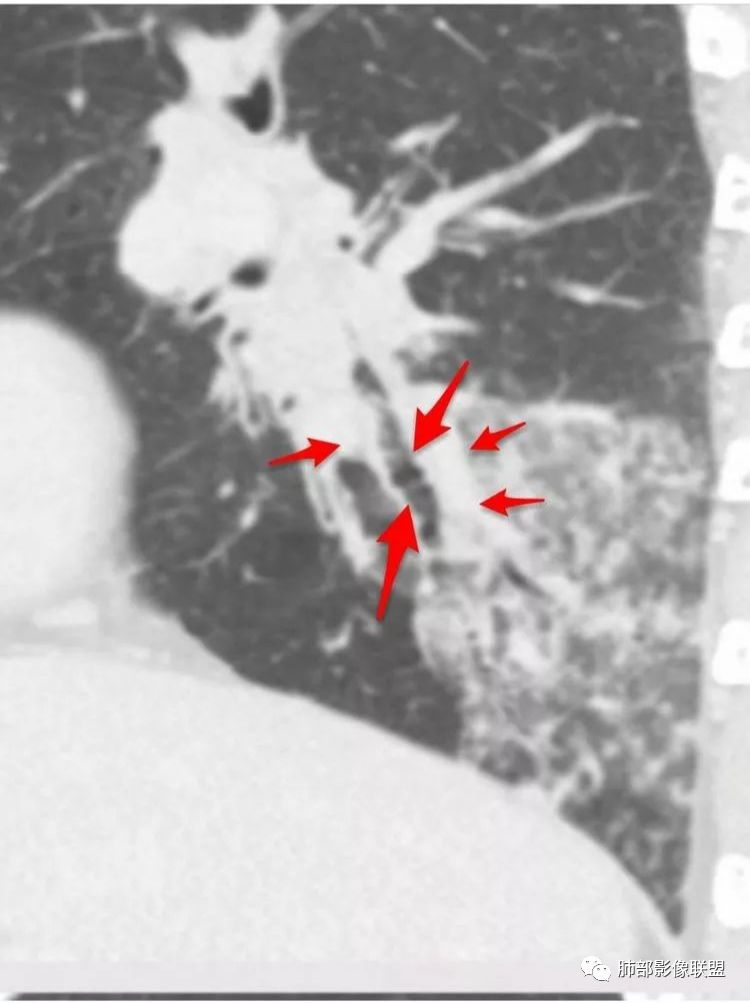

分布:沿支气管段、亚段朝外蔓延分布

实变区边缘收缩,支气管走形自然

但是我们也可以看到实变区很多地方没看到支气管,也就是支气管在实变区分布不均匀,提示有些地方支气管腔内有物质填塞,显示不清

因为病灶的分布就是沿支气管走形,病灶整体就是沿段分布

实变区边界清、凹陷及平直,内部密度均匀,强化均匀,支气管在密实处填塞,其余部分通畅、走形自然,中央间质均匀增厚

右肺门区淋巴结增大,融合,密度均匀,均匀强化

支气管没看到明显的堵塞

但是应该是与受压局部狭窄,导致远端引流不畅有关

吴倩南京市第一医院:第一个是分布的定位问题,南大把他分成三种,第一个肺实质肺泡来源的,第二个支气管从上面往下来的,第三个是间质来的。如图如果是肺泡本身发生的病变应该是外周大,实,往里面变小,变虚,还有支气管壁不增厚。

但是这个病例是由支气管往下,越来越淡,与支气管是平行走形,然后支气管壁增厚,还有树丫,虽然带着GGO的,分布属于支气管往下来的,这个和粘液腺癌不同,和肺炎链球菌也不同。比较符合TB,支原体这些。

中央间质的增厚和支气管壁增厚的问题,支气管壁其实它不是中央间质,支气管血管束、支气管周围的那些间质成分才是中央间质。它们的差异,中央间质是围绕血管、支气管周围,但支气管壁增厚是以支气管为主。我们一般来说横切面切到了紧隔的支气管、血管,除非它本身把支气管扩张独立出来,发现支气管周围壁的增厚程度和血管不对称。一般支气管、肺动脉伴行时大小是差不多的,发现支气管的周围外径明显大于血管外径,此时我们考虑支气管来源。支气管和血管束横切面时联系很紧密,周围一圈在一起,大小形态差不多,那就考虑中央间质来源的。前面分析的结节病分布特点如上,没有偏侧性。血管炎往往血管束增粗,比支气管厉害一些,当然也不是绝对的,大部分是这样的。

病灶明显按叶、按段分布为主的,或者跟气道进来的病原菌引起气道壁的改变为主的,周围实变引起的,看CT冠状位、矢状位,如果能够沿着长轴重建更明显,就是沿着典型肺段分布的特点,如果急性沿肺段分布一般考虑气道来源。当然该患者说间质性可不可以?也可以,但是这样分布间质性也有特点。但我们周围外围分布为主,不按从肺门向外围肺叶段分布的话,那我们考虑外围的,它长轴会和胸膜平行的概念,常认为间质的。还有肺实质病变,理解是有差异的,肺隐球菌是肺实质病变?肺间质病变?应该两者都有。因为病灶在肺间质里面的,往往大片间质性病变,都是弥漫性间质病变,很少局限的。如果局限的,往往和中央间质相关的,就淋巴道局限有可能肺门淋巴结堵塞引起逆流受阻、分流受阻。或者沿着肺门淋巴结朝外围逆行性增生性增长。一般肺间质对称的,为疏松结缔组织,肺部疏松结缔组织弹性更好,纤维成分、纤维细胞多。第二巨噬细胞多。纤维化病变与免疫及相关的有关,也有特发的。间质相关性往往是弥漫的,主要其所有细胞,包括基质、细胞是相连相通的,特性是一致的,局限受累的比较少。